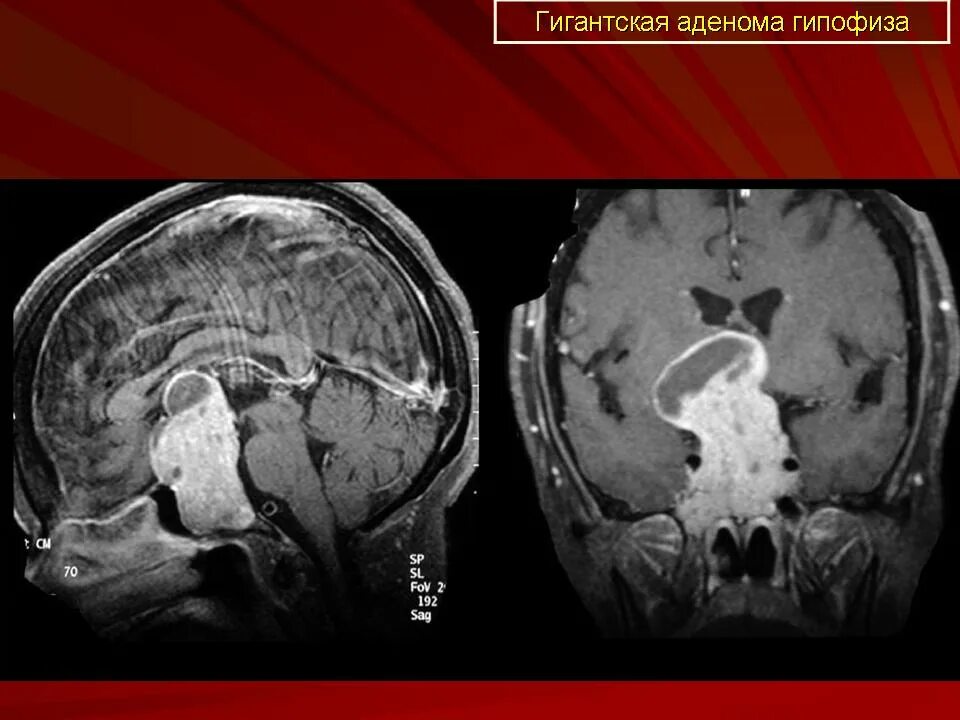

Опухоль гипофиза